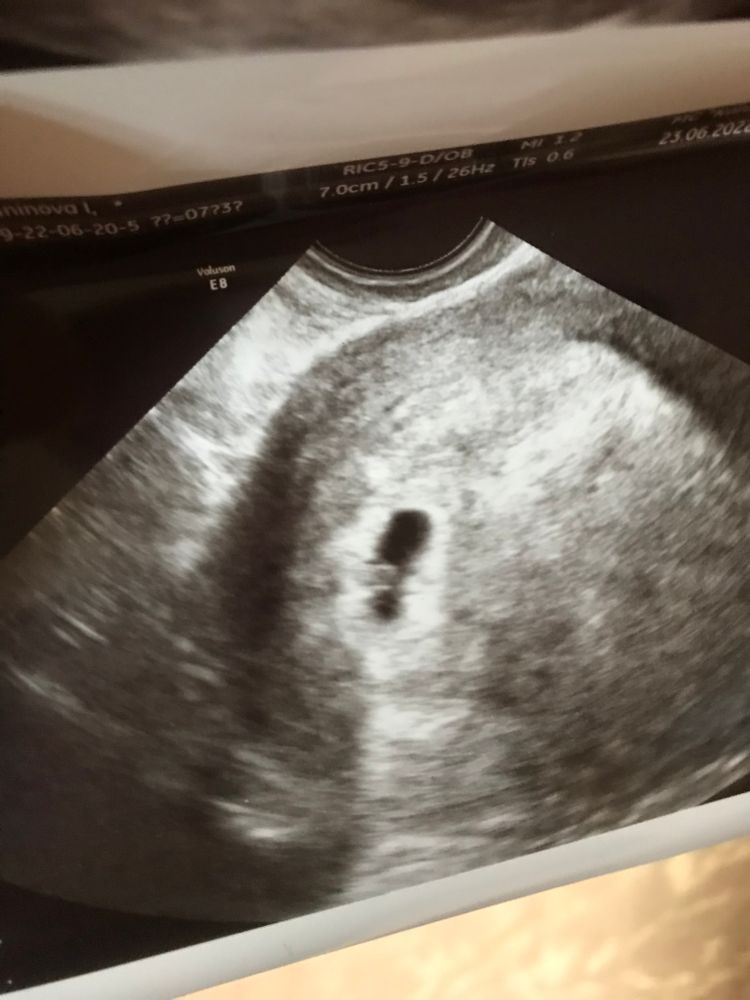

Всм нет шансов?????? Жм есть значит скоро эмбрион появится! Меняйте врача 🤦 Пусть держится за маму крепко 🙏

Максимова Елизавета, вот и я говорю, его же 3 дня назад не было. Она пригласила меня в понедельник. Надеюсь малыш уже появиться на экране!)))

Динамика есть! А по книге все быть не может. Поэтому на след узи увидите своего эмбриончика и сб+